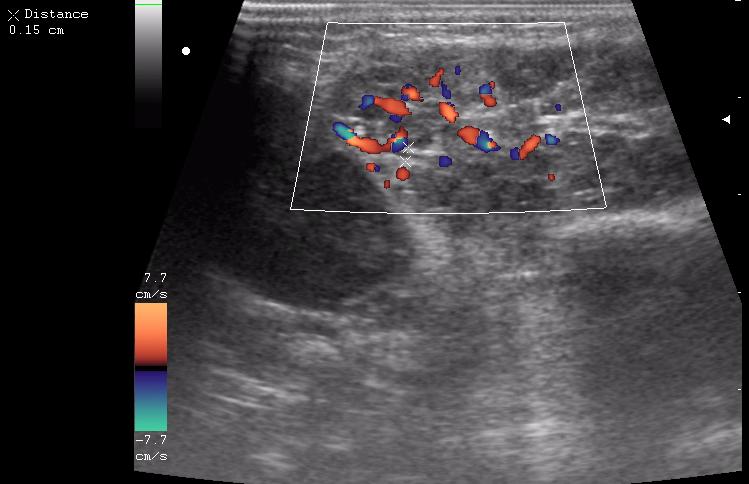

левая околоушная железа

левая поднижнечелюстная железа

правая околоушная железа

расширенный выводной проток